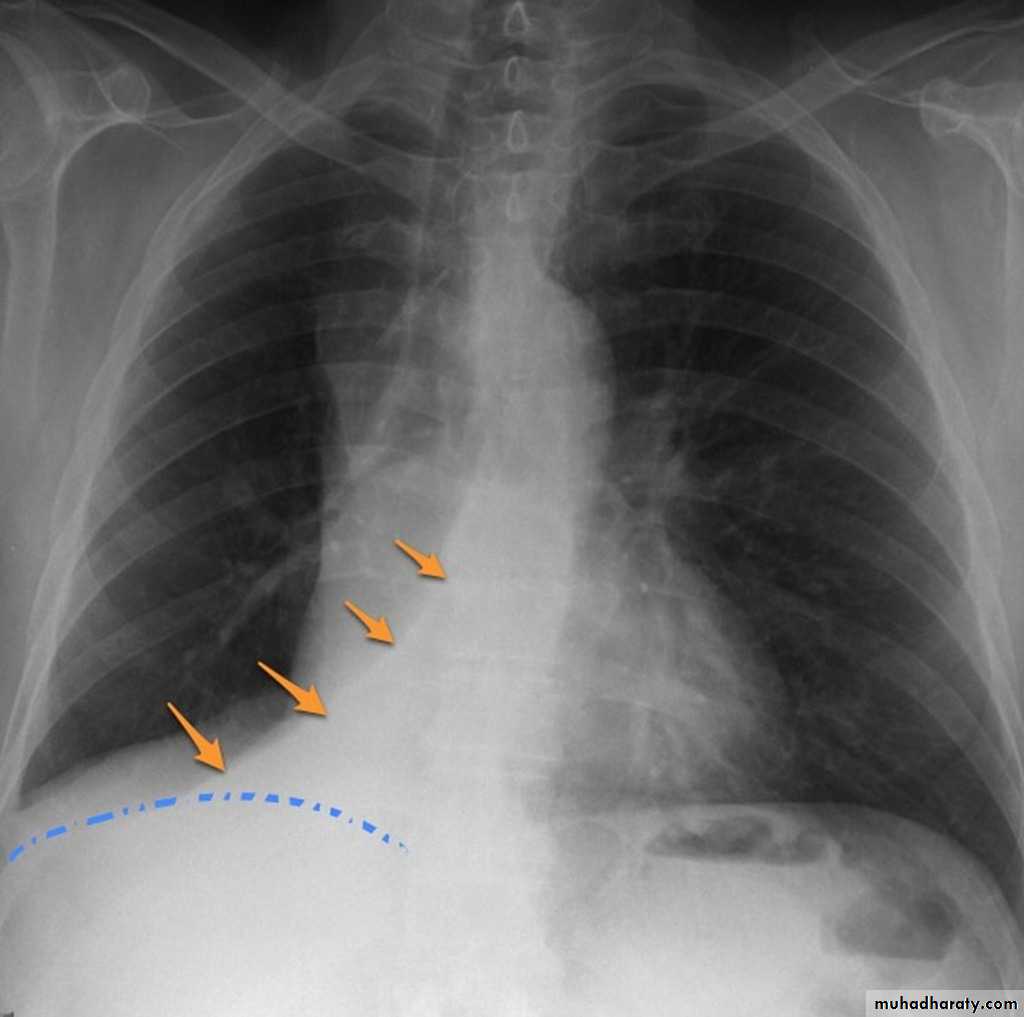

Pleural effusion

Pleural effusion tends to be used as a catch-all term denoting a collection of fluid within the pleural space. This can be further divided into exudates and transudates depending on the biochemical analysis of aspirated pleural fluid. Essentially it represents any pathological process which overwhelms the pleura's ability to reabsorb fluid.Radiographic appearances

Plain radiographChest radiographs are the most commonly used examination to assess for presence of a pleural effusion, however it should be noted that on a routine erect chest x-ray as much as 250-600 ml of fluid is required before it becomes evident 6. A lateral decubitus film is most sensitive, able to identify even a small amount of fluid. At the other extreme, supine films can mask large quantities of fluid.

CXR (erect)

Both PA and AP erect films are insensitive to small amounts of fluid. Features include:

blunting of the costophrenic angle

blunting of the cardiophrenic angle

fluid within the horizontal or oblique fissures

eventually a meniscus will be seen, on frontal films seen laterally and gently sloping medially (note:

A subpulmonic effusion (infrapulmonary effusion) may be seen when there is previously established pulmonary disease, but can also be encountered in normal lungs , They are more common on the right, and usually unilateral

with large volume effusions, mediastinal shift occurs away from the effusion (note: if coexistent collapse dominates then mediastinal shift may occur towards the effusion)